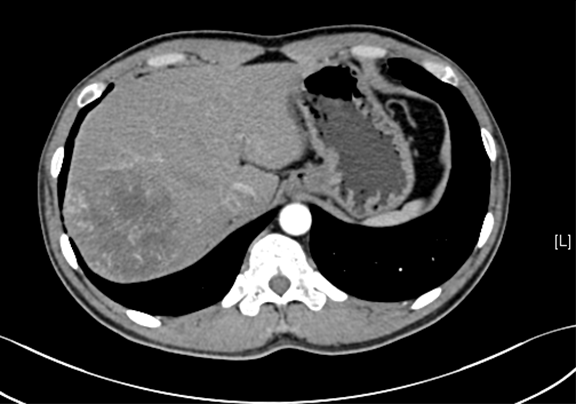

术前CT检查:

动脉期

静脉期

平衡期

下腹部增强CT示:肝右后叶占位性病变,考虑肝癌可能性大。

现病史:患者于6天前无明显诱因出现右上腹疼痛,呈持续性,伴乏力,食欲减退,腹胀,无恶心、呕吐、腹泻、血便、无寒战,无头痛头晕,无皮肤粘膜黄染,无尿频、尿急、尿痛、血尿。曾于莱西人民医院就诊,行消化系B超示:右叶后外段见一稍高回声结节,大小约6.7*6.7cm,行上腹增强CT示:肝内占位,肝Ca可能性大。大便次数减少,体重减轻3斤。